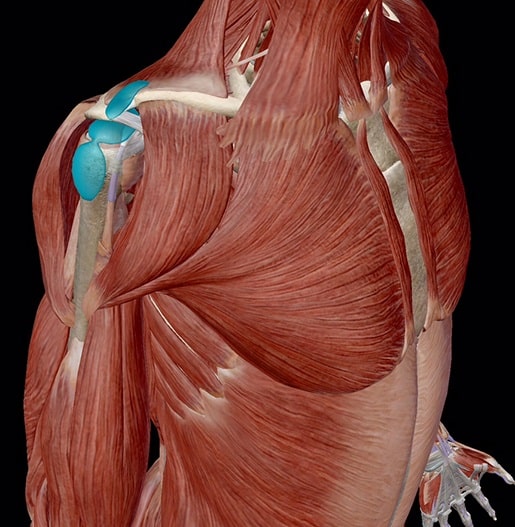

آناتومی

شانه شامل سه استخوان است: استخوان فوقانی بازو (هومروس)، استخوان کتف ( اسکاپولا) و ترقوه ( چنبر یا کلاویکول).

سر استخوان فوقانی بازو به درون گودی کاسهای به نام گلنوئید در استخوان کتف قرار میگیرد. ترکیبی از عضلات و تاندونها که شانه گردان یا روتاتور کاف نامیده میشود، استخوان بازو را در مرکز گودی کاسهای شانه نگه میدارد. عضله شانه گردان، سر استخوان فوقانی بازو را میپوشاند و آن را به استخوان کتف متصل میکند.

درون مفصل شانه، کیسه کوچک حاوی مایعی وجود دارد که بورسا (bursae) نامیده میشود. هدف آنها فراهم کردن بالشتکی بین مفاصل است، که به کاهش اصطکاک بین عضلات و استخوانها در مفصل کمک میکند.